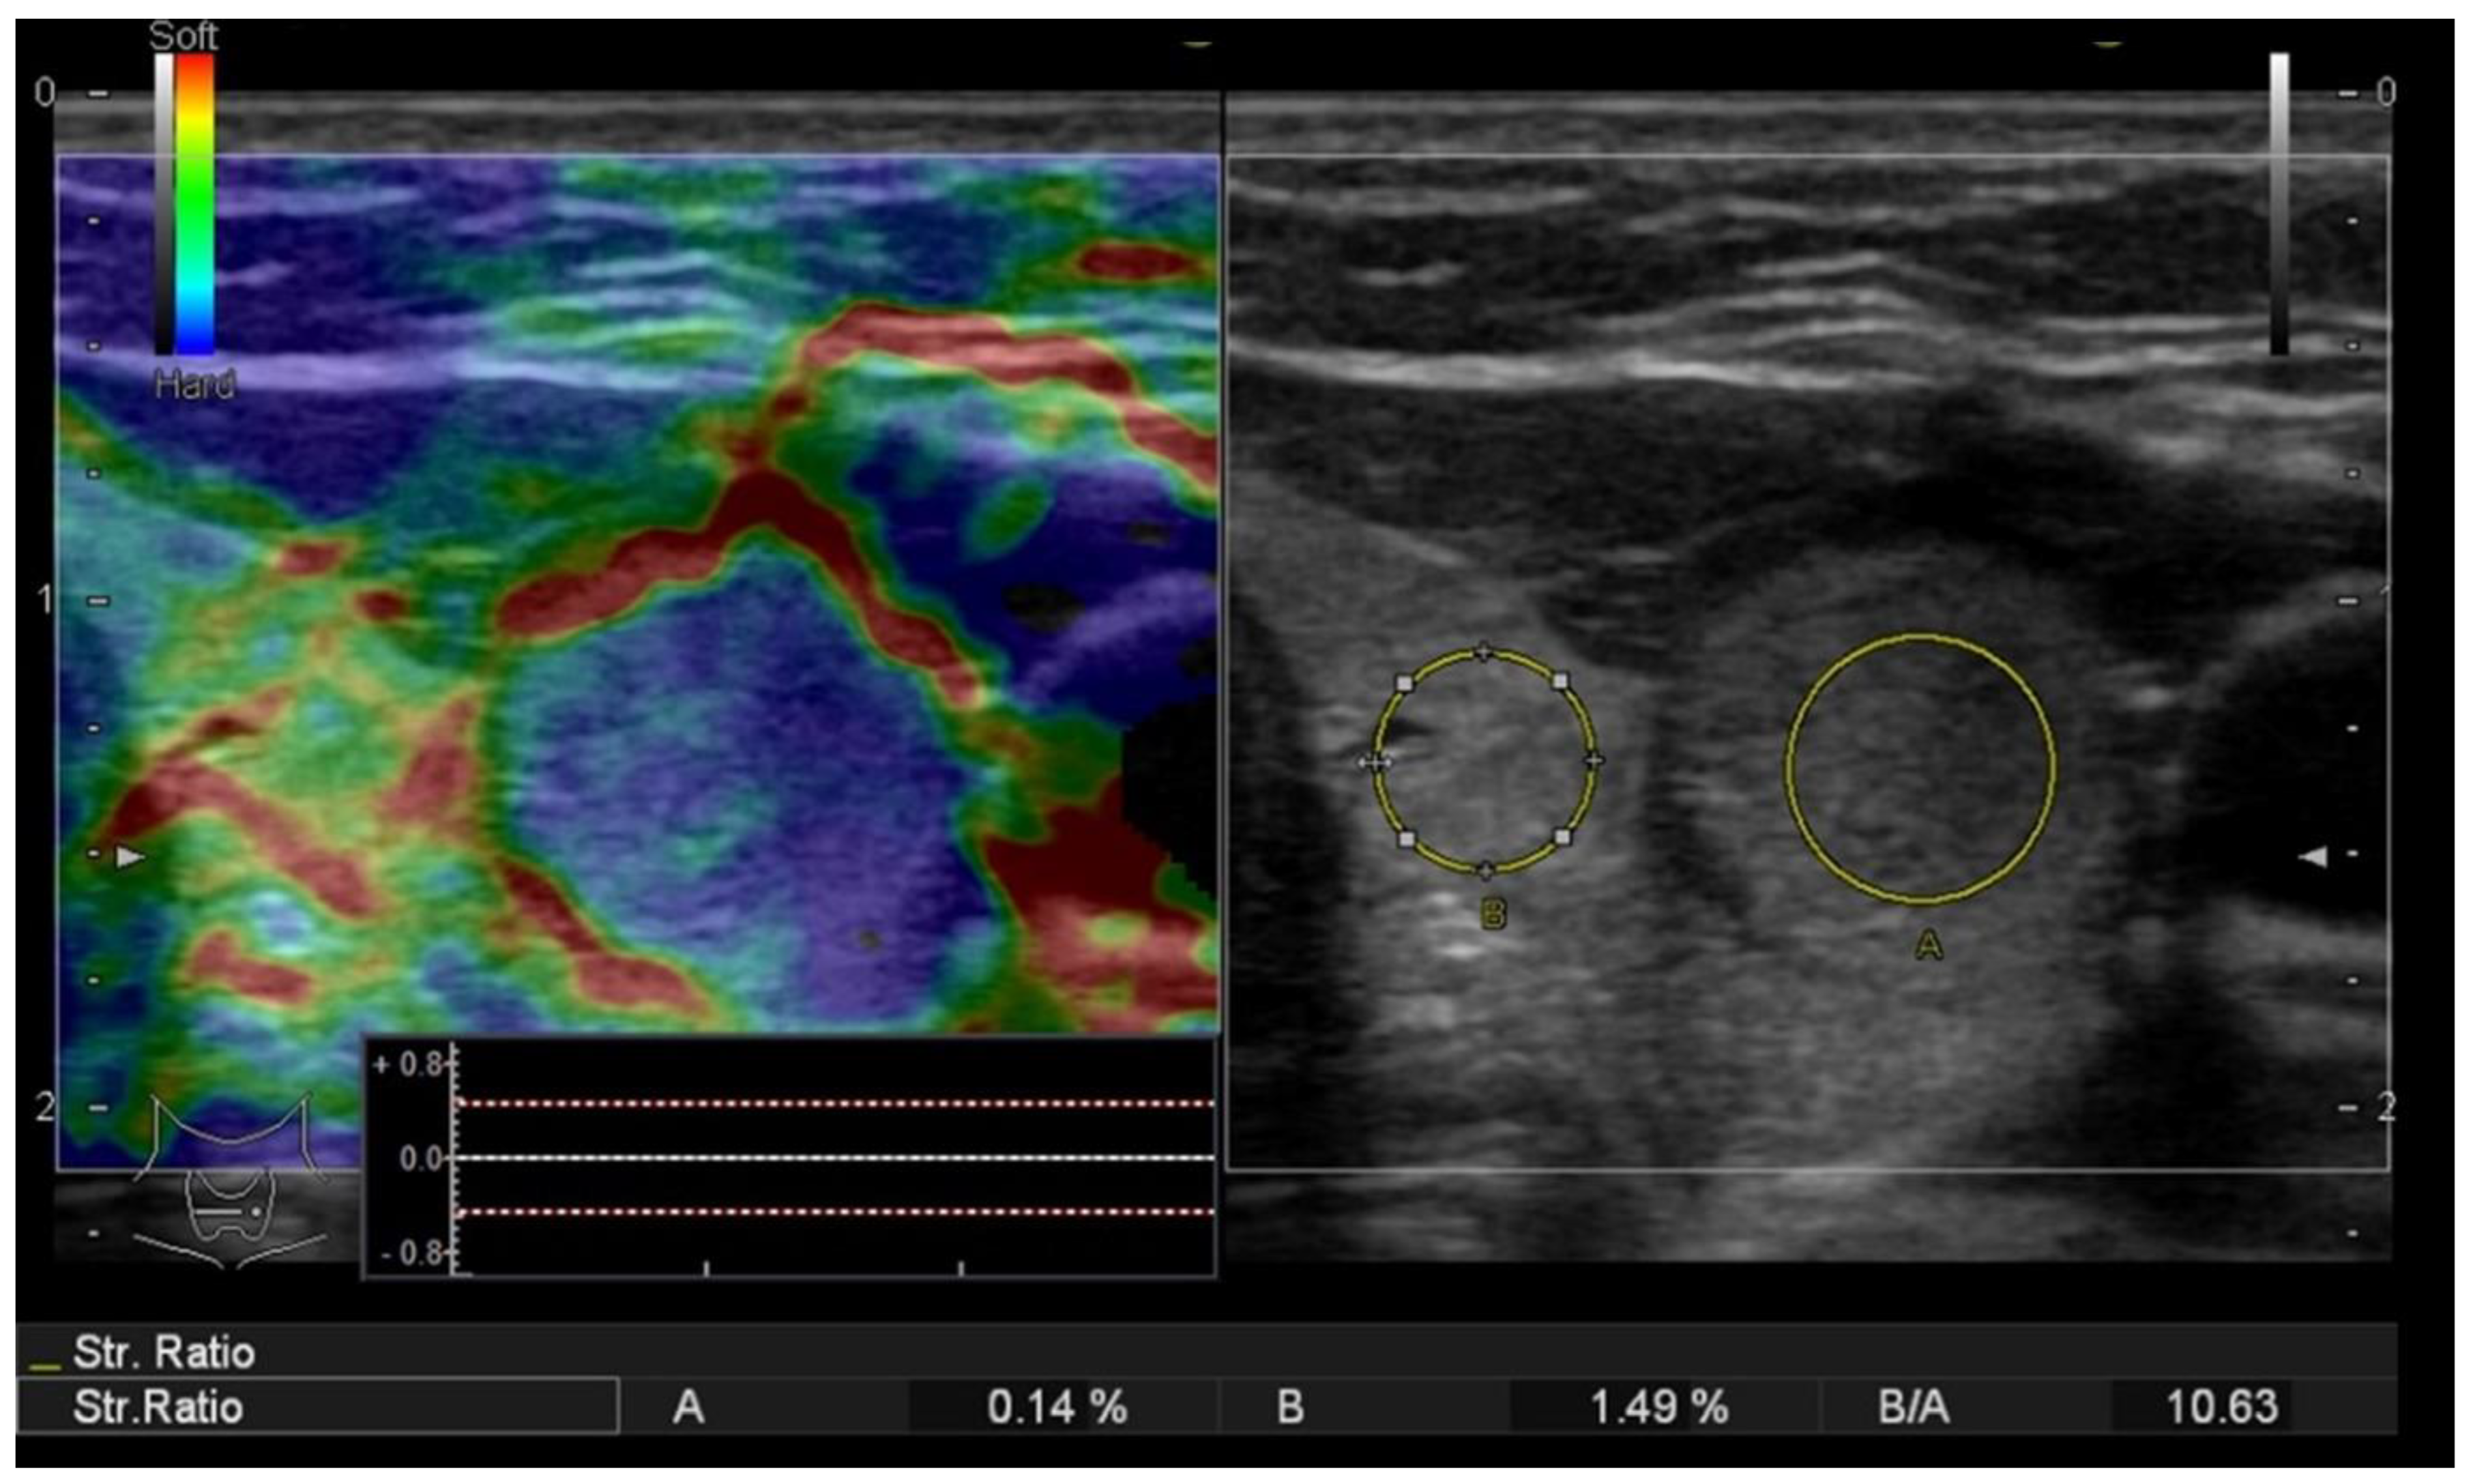

A risk upgrade was made in 14 cases with increased stiffness, defined as values of the SR above 3.9: an upgrade of the risk category from low to intermediate was made in 4 cases and medium to high risk in 10 cases (see Figure 6).

Figure 6.

Risk upgrade from intermediate risk in B-mode to high risk in B-mode + SE due to increased stiffness (Asteria 3). Pathology report confirmed PTC.